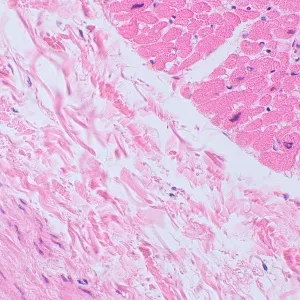

Микроскоп MAGUS Bio 250BL может использоваться и для рутинной работы в лаборатории, и для научных исследований, и для обучения студентов. Он предназначен для работы с тонкими срезами и мазками биологических образцов в проходящем свете. Основной метод наблюдений – светлое поле, но возможно и использование темного поля, поляризованного света и фазового контраста (при установке дополнительных компонентов).